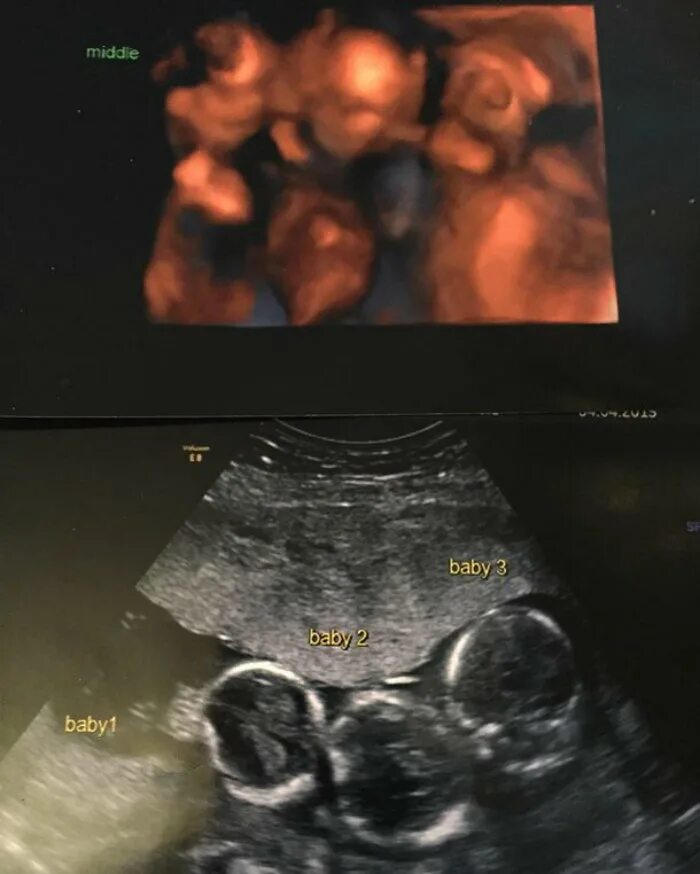

На каком сроке можно увидеть двойню